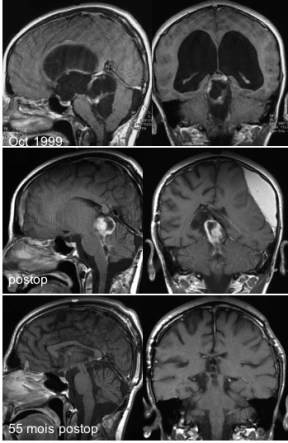

c’est un moyen efficace de prévenir les récidives, et même de faire disparaître un reliquat tumoral postopératoire non extirpable (ci-contre) ; elle est cependant grevée de morbidité en raison de sa neurotoxicité chez les jeunes enfants et du risque de tumeur radio-induite.